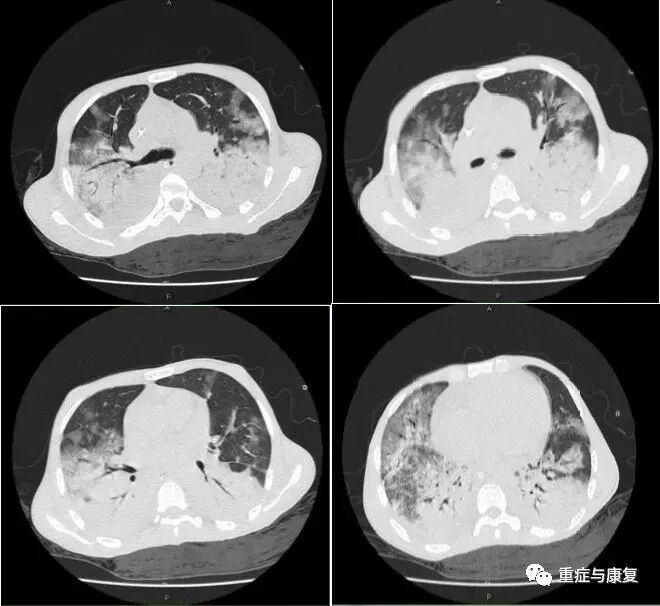

患者病情继续加重,次日出现深昏迷,全身皮肤巩膜深度黄染,复查肝功能:TBIL 518.4umol/L,DBIL 267.9umol/L,ALT 143U/L,AST 151U/L,ALP 118U/L;血氨:93umol/L;血气分析示OI 122。即进行血浆置换治疗,共4次(5/6-8/6),神志转清,胆红素水平较前明显下降,血氨下降。06-12因患者气促明显,PCT明显上升,并出现皮疹,考虑肺部感染进展,且不排除药疹可能,抗感染方案调整为美平、利奈唑胺、米卡芬净,继续积极的综合治疗,患者病情有好转,热退,肺部感染、肝功能不全逐渐好转,血氧改善,2015-06-17复查肝功能基本降至正常(TBIL 29.7umol/L,DBIL 12.1umol/L,ALT 38U/L,AST 40U/L),床边照片及胸部CT均提示肺部炎症明显吸收(图1-2,图1-4);于6-20成功脱离呼吸机拔除气管插管。

图1-4 胸部CT(复查,2015-6-17)